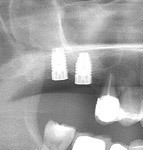

- Cas 1: Le comblement sinusien maxillaire consiste à créer un volume osseux dans le sinus maxillaire pour y ancrer des implants.

Une poudre d’os est placée pour combler le sinus maxillaire et permettre la pose d’implants.

Des membranes de PRF sont placées pour épaissir la muqueuse sinusienne et refermer la fenêtre et recouvrir les implants enfouis. Après l’extraction des prémolaires et molaires maxillaires, un comblement sinusien est nécessaire une fois sur deux pour poser des implants de 10 mm de longueur.